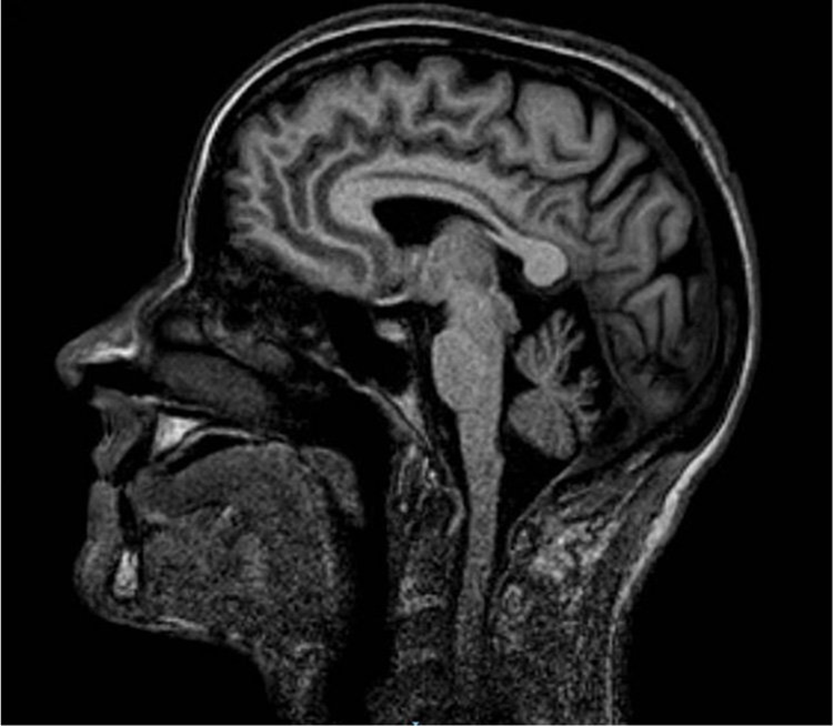

Los trastornos mentales orgánicos son definidos en la CIE-10 ,Clasificación Internacional de Enfermedades ,como un conjunto de desórdenes psicologicos y de conducta originados por la pérdida o una alteración, estructural o funcional del tejido cerebral.

Los trastornos mentales organicos pueden ser clasificados en primarios o producidos por un daño cerebral como una lesión traumática y secundarios o derivados de otras enfermedades sistémicas u orgánicas como los originados por el abuso del alcohol o drogas psicoactivas.

Dentro de los desórdenes orgánicos podemos citar la demencia, el delirium tremens, síndrome amnésico orgánico, la alucinosis orgánica, el trastorno esquizofreniforme orgánico y el afectivo trastorno afectivo orgánico aunque también existen diversos trastornos de personalidad o del comportamiento que tienen su origen en algún daño cerebral.